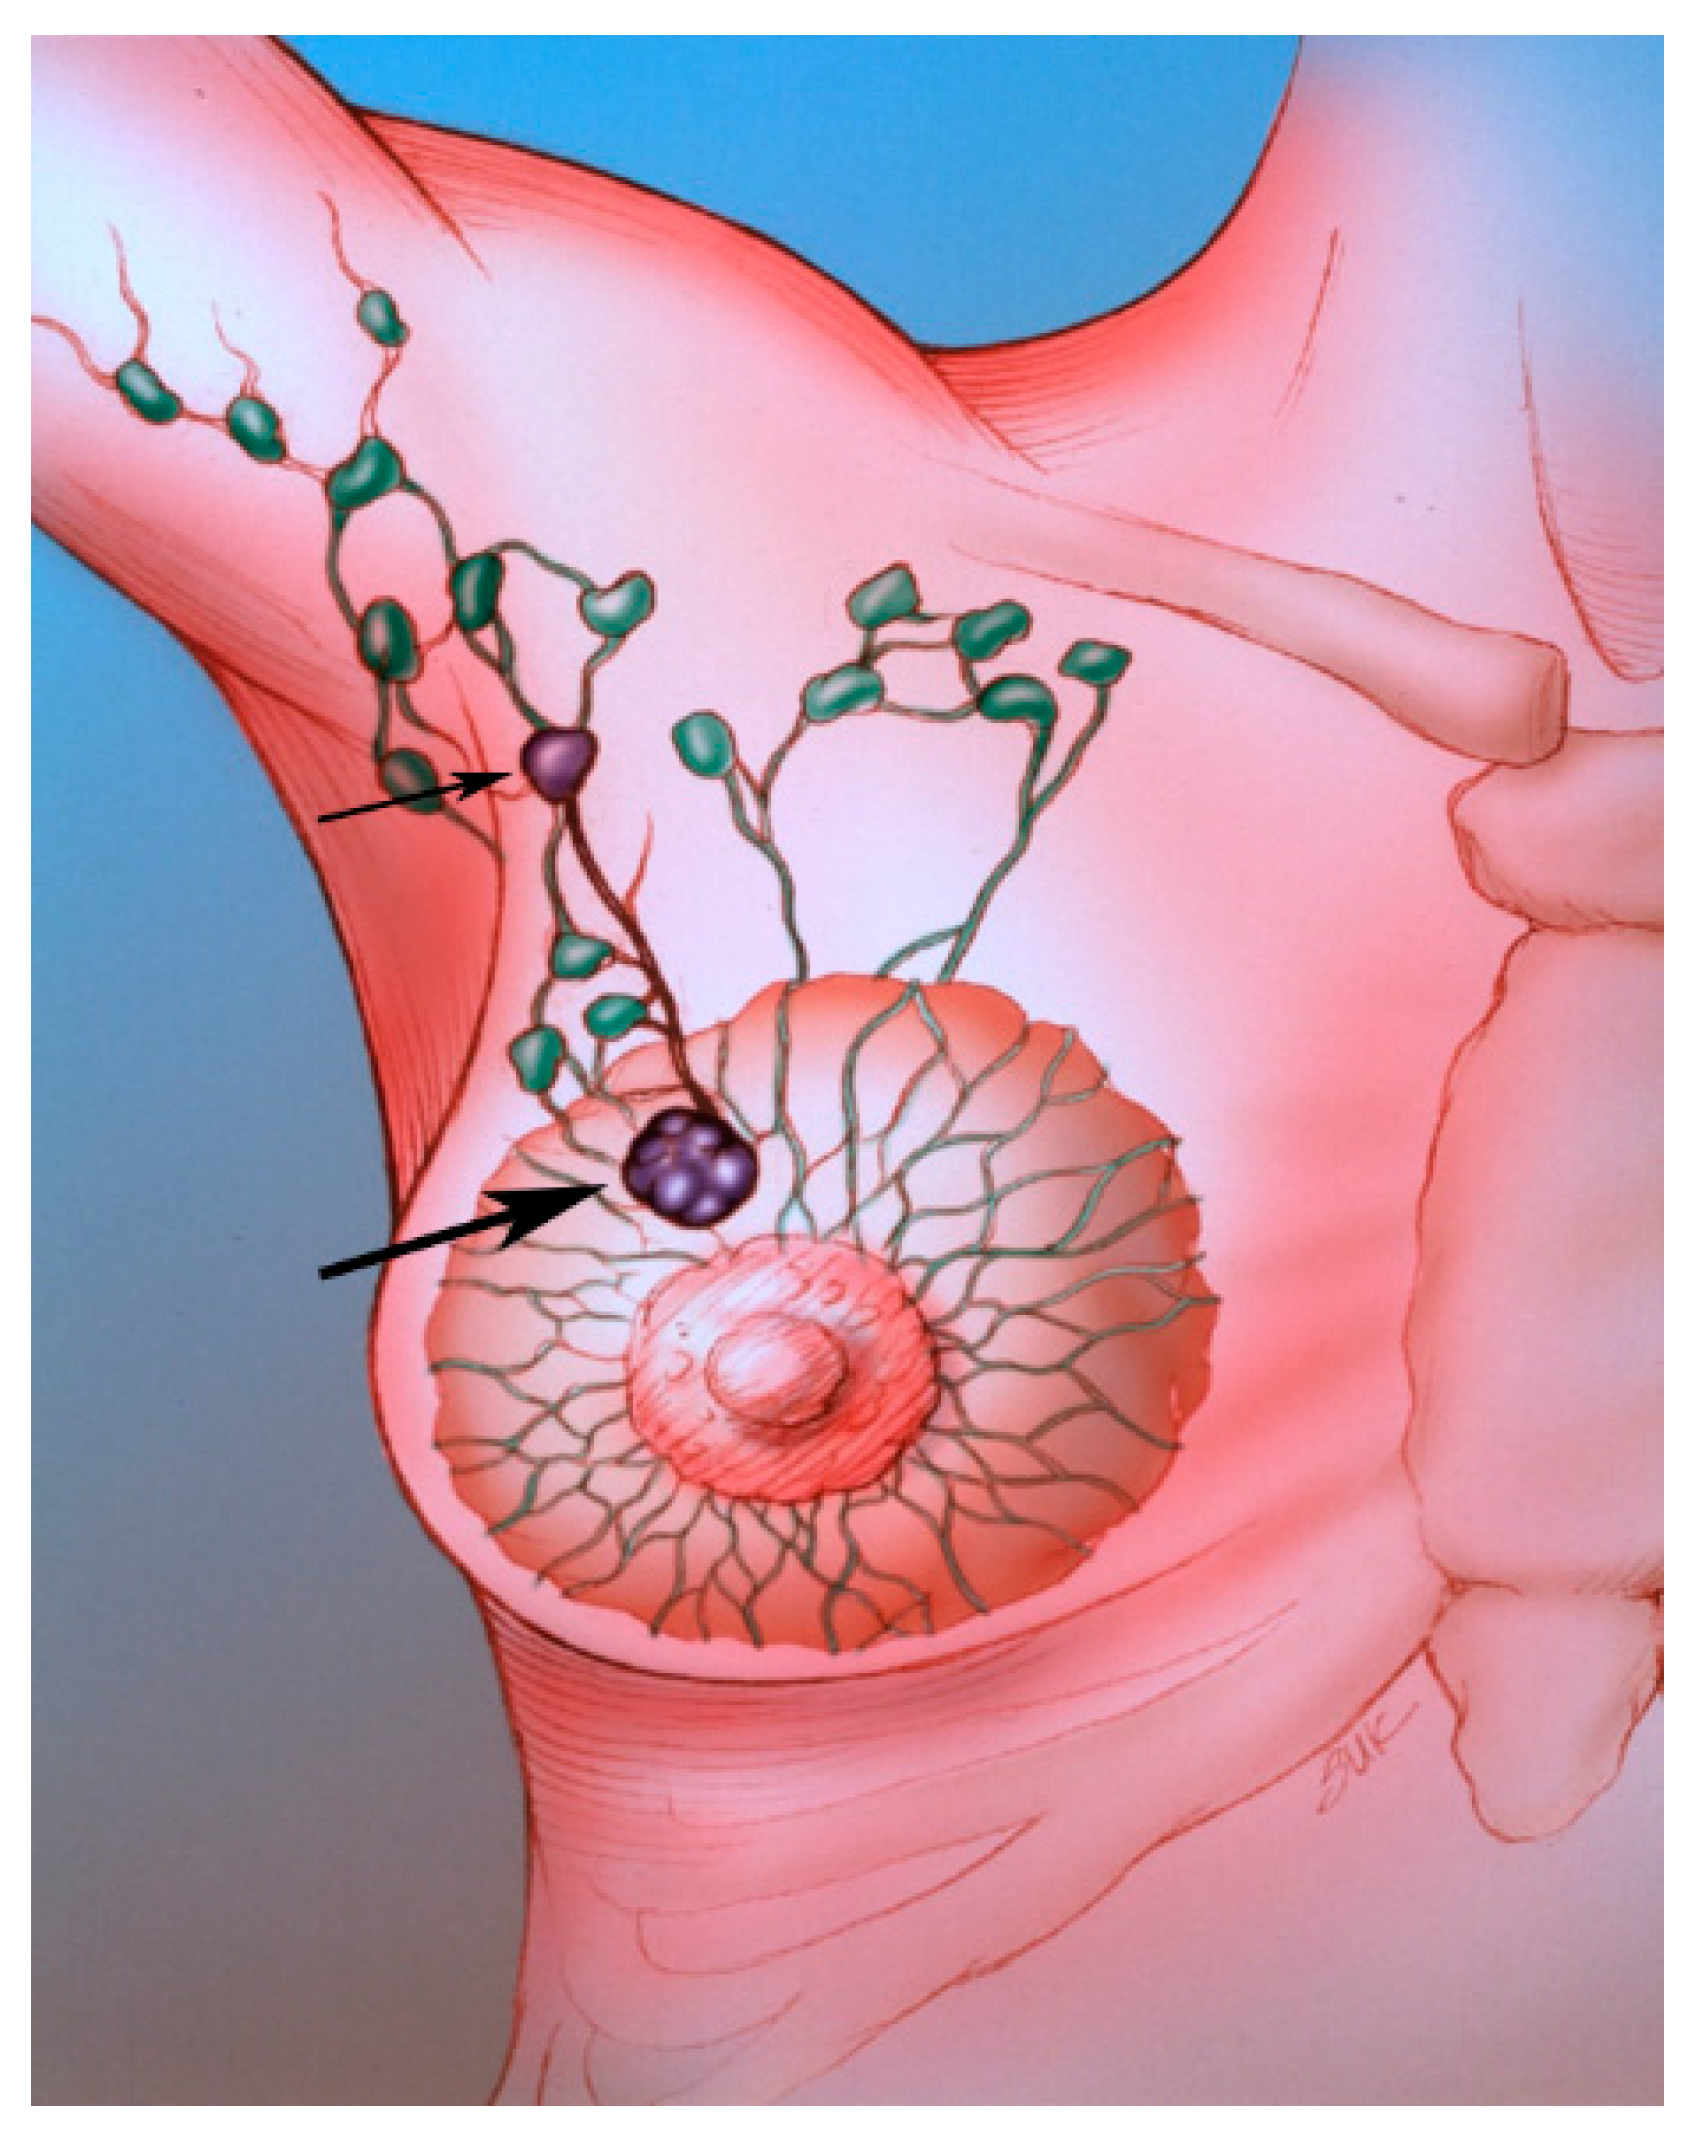

Figure 2. The SLN (small arrow) is the first lymph node draining the tumor (large arrow).

Sentinel lymph node biopsy (SLNB) has become standard in patients being treated for breast cancer with clinically negative lymph nodes [4]. The sentinel lymph node (SLN) concept (Figure 2), which states that the histologic status of the SLN is predictive of the status of the regional lymph nodes, is based on the orderly spread of tumor from the tumor bed to the regional lymph nodes. Sentinel lymph nodes (SLNs) are defined as the first group of lymph nodes draining the tumor bed. The SLNs can be located by injecting blue dye and/or radioactive material at the tumor site and subsequently, identifying a blue (Figure 3) and/or a radioactive lymph node in the axilla. Originally proposed in the management of penile cancer by Cabanas [5] in 1977, the SLN concept has been applied in patients with malignant melanoma [6] with considerable success. The American College of Surgeons Oncology Group (ACOSOG) Z011 trial compared two groups of clinical T1–2 N0 M0 breast cancer patients with a positive SLN [7]. The patients were treated with lumpectomy and opposing tangential field radiation therapy and adjuvant systemic therapy at the discretion of the treating physician. One group was randomized to SLNB without axillary dissection. The other group was randomized to SLNB followed by completion axillary dissection. The SLNB only group did not show inferior survival rates compared to the axillary lymph node dissection group [7].